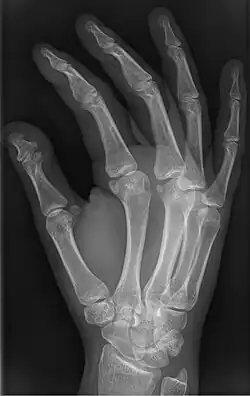

Brachyphalangy of the thumb's distal phalanx, also known as brachydactyly type D, with otherwise normal phalanges of the 2nd-5th digits | |

Brachyphalangy is a condition in which one or more of the phalanges of the fingers and toes are smaller than normal.[1]

This condition is one of the most common non-syndromic causes of brachydactyly and clinodactyly.